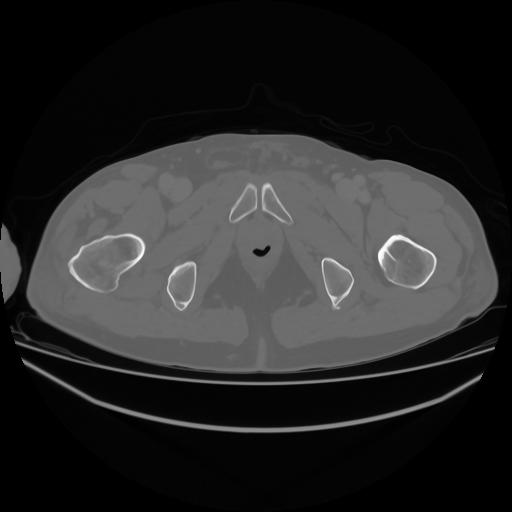

4 CUERPO,CE,Axial,3.0,CUERPO,,